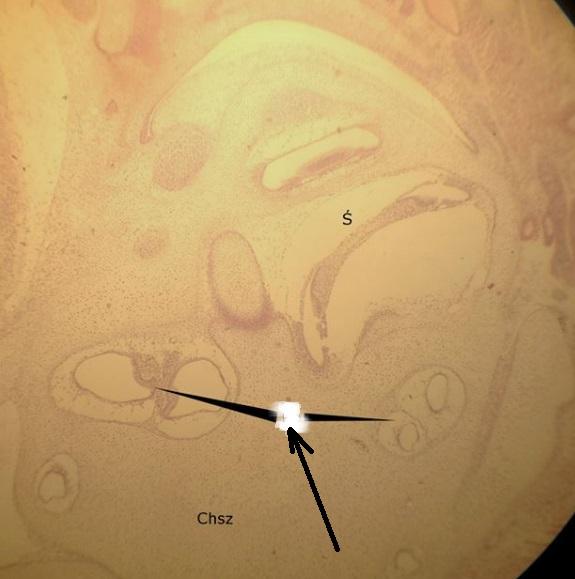

Pytanie 361

chrząstka szklista (preparat rozwojowy z głowy szczura, okolice zawiązka mózgu)